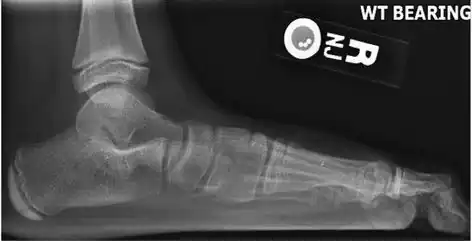

Weight-bearing lateral X-ray showing the measurement of calcaneal pitch, which is an angle of the calcaneus and the inferior aspect of the foot, with different sources giving different reference points.[13] A calcaneal pitch of less than 17° or 18° indicates flat feet.[11] -

Same lateral X-ray showing the measurement of Meary's angle, which is the angle between the long axis of the talus and first metatarsal bone.[11] An angle greater than 4° convex downward is considered a flat foot, 15° - 30° moderate flat foot, and greater than 30° severe flat foot.[11]